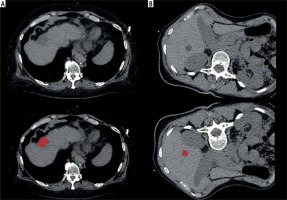

Computed tomography images were further analyzed with the dedicated software MaZda (version 4.7, available at http://www.eletel.p.lodz.pl/mazda/) [19, 20]. A region of interest (ROI) was drawn on the largest slice of the target lesion. The ROI was drawn within the liver lesion with 2 mm distance to the adjacent parenchyma. Texture analysis measurements were blindly taken for the bioptic and clinical results. For each ROI, gray-level (µ) normalization was utilized to µ ±3 standard deviations to reduce the influence of contrast and brightness variation on the texture features, as performed previously [16, 17]. Texture features of various groups were extracted for each patient including histogram parameters, second order texture features of different groups comprising co-occurrence matrix run-length matrix, absolute gradient, autoregressive model (theta 1 to 4, sigma), and wavelet transform features. Altogether, 279 texture features were calculated in all lesions. Two representative cases of the patient sample are shown in Figure 1 with the drawn ROI.

Fig. 1

Representative cases of the patient sample. A) 68-year-old female patient, no steatosis, no fibrosis, diagnostic biopsy with benign result, platelet count 316,000/μl, distance to liver capsule 0 mm, no hemorrhage. B) 61-year-old female patient, steatosis degree 5%, minimal fibrosis, non-diagnostic biopsy, platelet count 81,000/μl, distance to liver capsule 13 mm, no hemorrhage